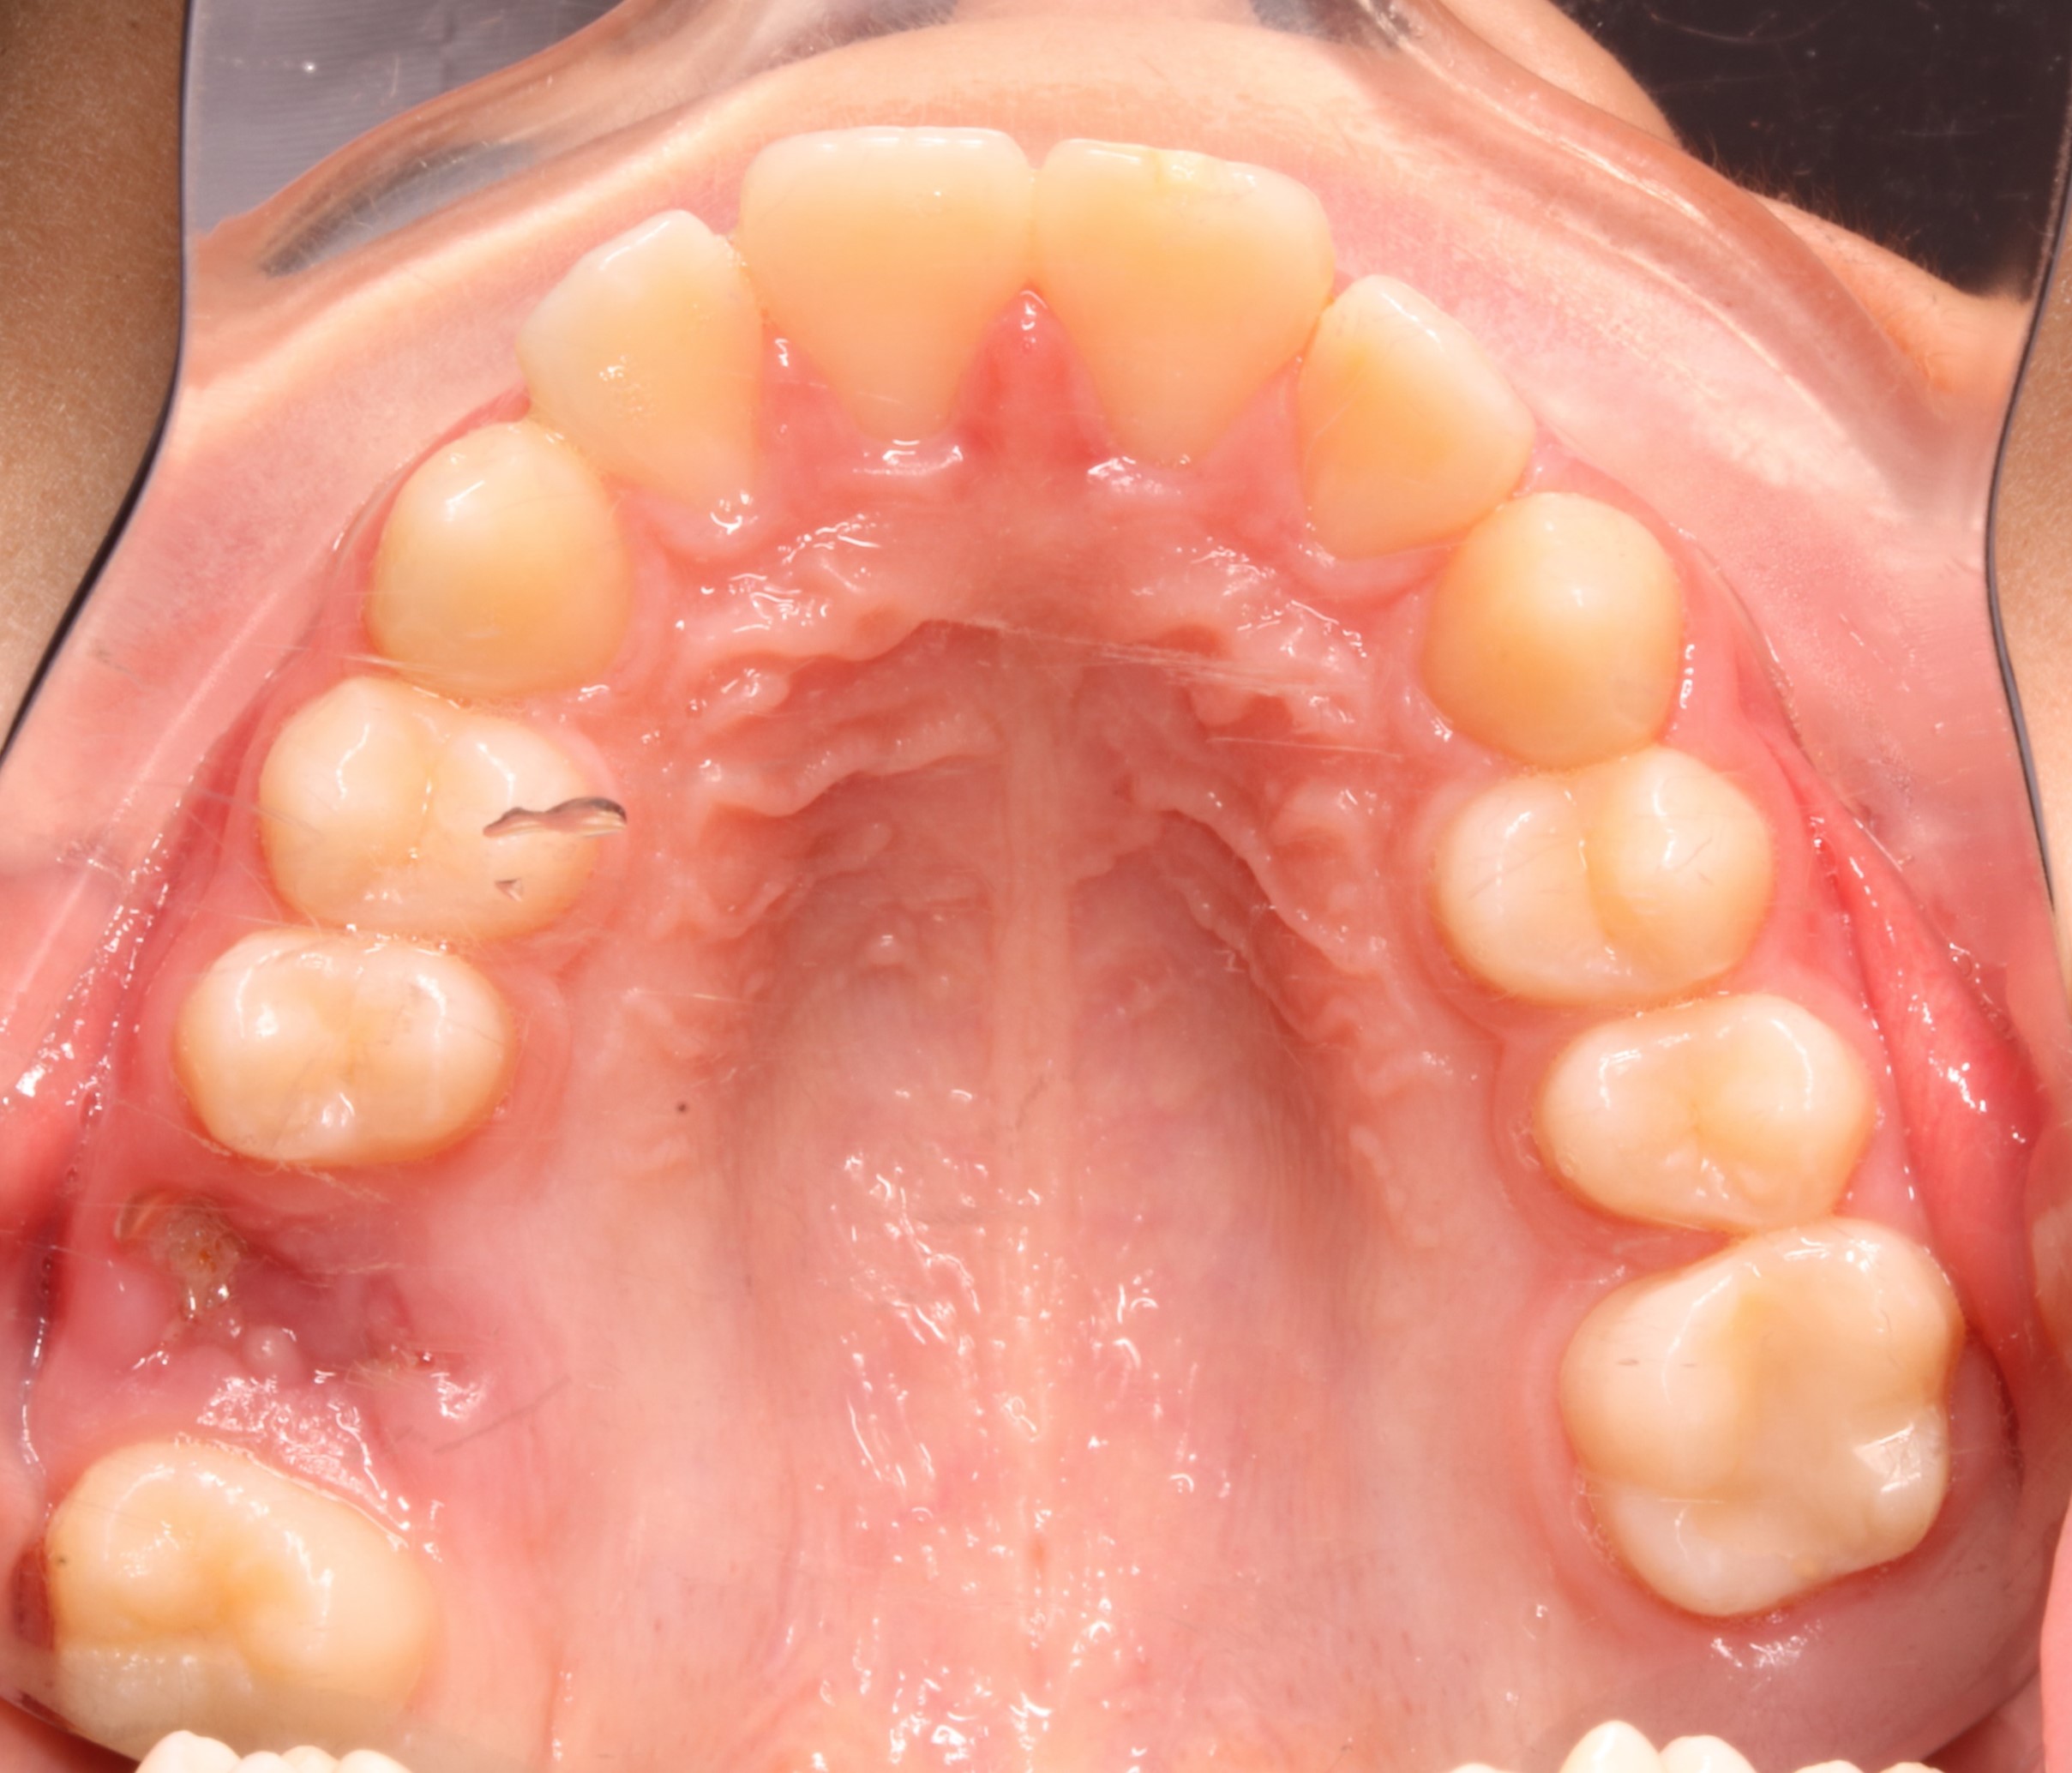

Nos encontramos con un caso en un timming adecuado para realizar un avance mandibular. También, nos favorece la inclinación el ángulo goniaco de 123 grados y la motivación del paciente. En contra nos perjudica la inclinación del incisivo inferior de 100 grados (lo podríamos controlar con microimplantes en la meseta inferior o alineadores, pero el paciente rechaza ambas opciones). Por otra parte,  en la radiografía frontal observamos un resto radicular en el 16, que decidimos extraer, y a petición del paciente, cerrar el espacio con mesialización del 17.

BORDE IRREGULAR EN 21 RECONSTRUCIÓN AL FINAL DE TRATAMIENTO